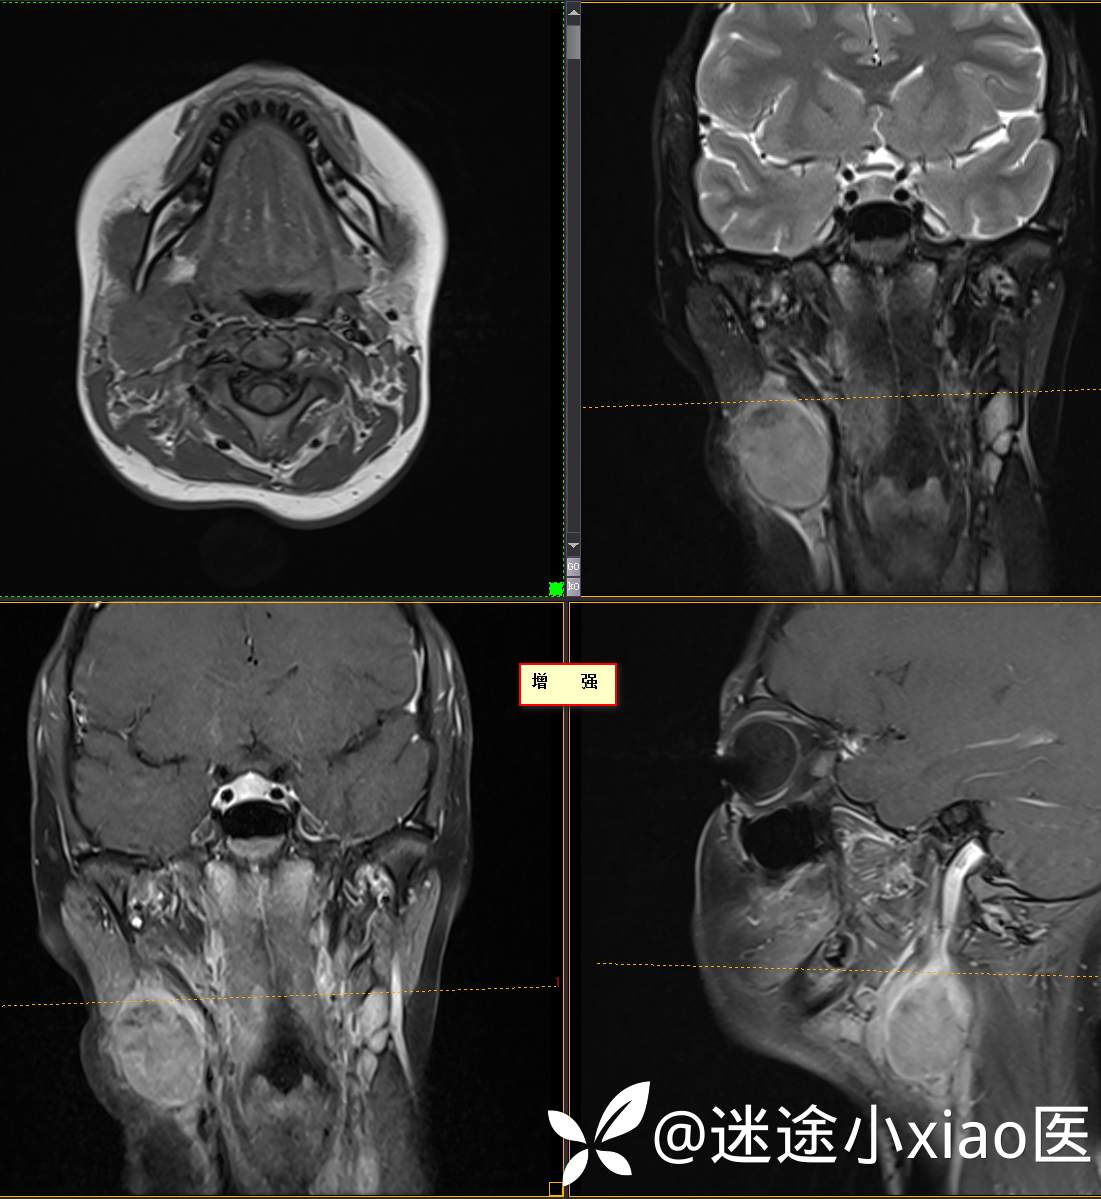

头颈组16:青少年女性,发现右颈部肿物半月余,感染?肿瘤?

主 诉:发现颈部肿物半月余

现病史:患者半月余前无明显诱因下发现右颈部肿物,大小4.2*2.1cm,局部无红肿,皮温正常,有压痛,感头晕头痛,无其他不适。查甲状腺及颈部淋巴结B超提示:双侧甲状腺多发结节;右侧多发肿大淋巴结。初步诊断为“淋巴炎”,予“头孢类”抗生素抗感染治疗12天(具体药物不详),自觉肿块胀痛缓解,头晕头痛症状仍存。